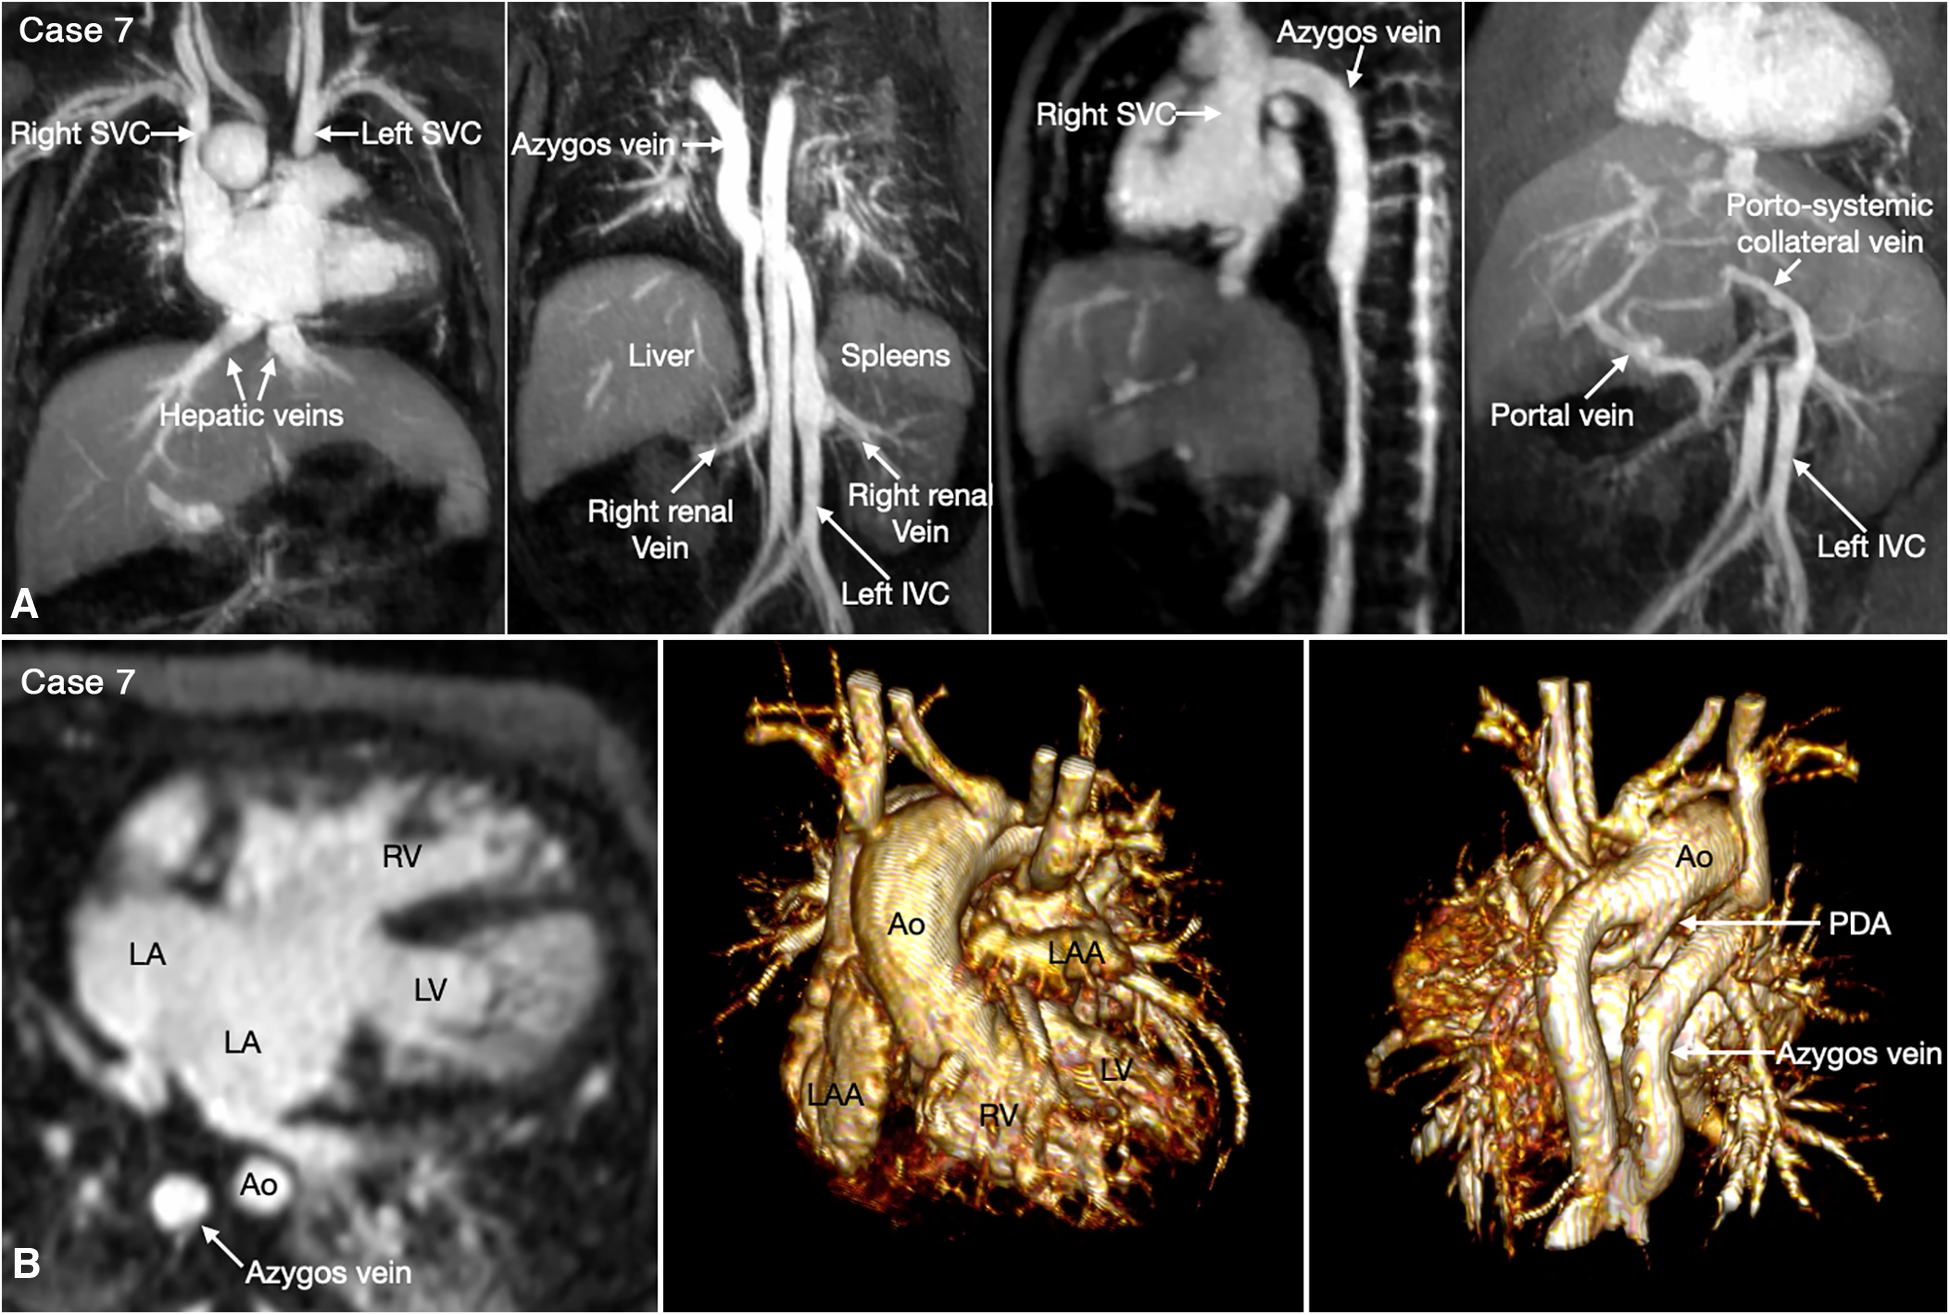

Figure 7

(Case 7). Complex systemic venous anatomy and extrahepatic portosystemic shunt in a patient with heterotaxy and left isomerism. (A) Maximum intensity projection (MIP) images show that the left inferior vena cava (IVC) is interrupted and continues to the left-sided (hemi)azygos vein. It then obliquely ascends to the right-sided azygos vein that connects to the right superior vena cava (SVC). The right renal vein also connects to the right-sided azygos vein through a vertical channel. Right panel shows a tortuous collateral channel connecting the unobstructed portal vein and the inferior vena cava. (B) MIP image in 4-chamber plane and volume rendered images in frontal and posterior superior views. Middle panel shows bilateral morphologically left atrial appendages (LAA). Left panel shows a large atrioventricular septal defect. The pulmonary veins are connected to the posterior wall of the common atrium. Middle panel shows both aorta (Ao) and severely stenotic pulmonary arterial trunk arising from the right ventricle (RV). Right panel shows a patent ductus arteriosus (PDA) arising from the undersurface of the aortic arch and connecting to the confluent pulmonary artery. LA, left atrium; LV, left ventricle.

Heterotaxy with left isomerism is often associated with extrahepatic portosystemic shunt (29, 30). As the portosystemic shunt results in chronic liver disease with portal hypertension and hepatic encephalopathy, its early recognition is important. 3D or 4D MR angiography is very helpful in visualization of the portal venous anatomy and collateral pathways owing to its wide field of view and homogeneous opacification of the vessels (Figures 7,8 Cases 7 and 8).